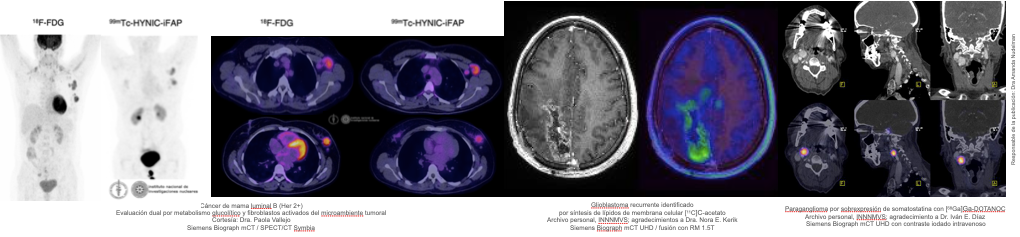

Son los fármacos propios de la Medicina Nuclear. Se constituyen por la unión de un isótopo radiactivo con una molécula dirigida a blanco o vía específica, que indican y permiten observar, caracterizar y cuantificar un proceso biológico mediante la determinación de la concentración regional del agente (permitiendo comparaciones ínter e intrasujeto). Los radioisótopos de gammagrafía/SPECT y PET producen, en su decaimiento radiactivo, de forma delimitada y segura, la emisión de rayos gamma o positrones -antipartículas positivas de los electrones y cuya aniquilación produce fotones de coincidencia-, que son detectados por los equipos, procesados por el sistema eléctrico para la conformación de imágenes, que posteriormente son evaluadas por médicos especialistas para realizar un diagnóstico clínicamente oportuno.